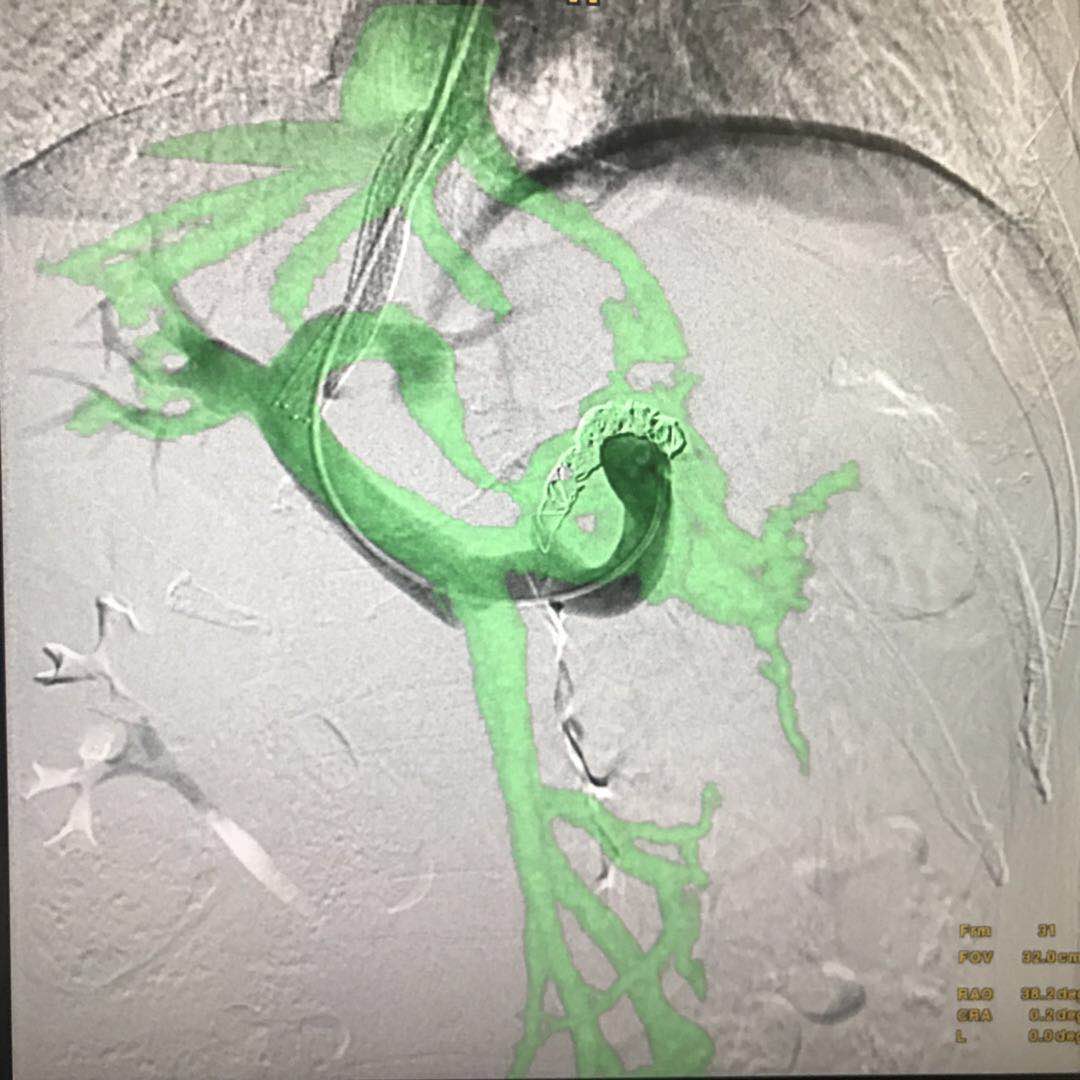

要想安全、准确地完成TIPSS手术,对术者的技术要求非常高。手术前,术者要通过术前的影像学资料:上腹部增强CT或MRI非常明确肝静脉和门静脉的解剖位置关系:即穿刺针进入到肝静脉后,术者要在头脑中把影像学中两者的前后左右位置关系转换成进针角度,把两者的距离远近转换成穿刺深度。如果对角度把握不准确,则很难穿中门静脉;如果对距离远近估计有误,穿刺深度不够时很难穿中门静脉,穿刺过深时,一旦穿刺到肝外门静脉,则容易出现术中腹腔大出血,严重威胁患 的呢?操作步骤非常简单:1、获得患者术前上腹部CTA/MRA图像,以此为基础,将患者的椎体、肝静脉和门静脉生长出来;;2、在透视下,用骨性标志和术中患者的实际位置进行配准对位,这样生长出来的肝静脉和门静脉的模型与患者实际的血管解剖部位自然也就配准了。不仅如此,在导丝进入肝静脉后我们还可以将肝静脉的模型和患者再次进行精准对位3、在透视下,我们可以直接按照智能路图来对着门静脉的方向进行穿刺在此过程中,只要患者相对于导管床的位置不变,无论机架角度和导管床的位置如何变换,智能路图的影像与机架和导管床都是联动的,无需重新对位置,不用担心模型与实际血管错位,如此大大方便了医生从各个角度观察门静脉的走形和位置,及时调整穿刺针的角度和深度。 本周在河南某医院进行了影像融合下引导TIPSS手术,大大提高了手术精度,最大程度地降低了手术风险,减少了操作时间,提高了术者信心。手术图像详见下图: